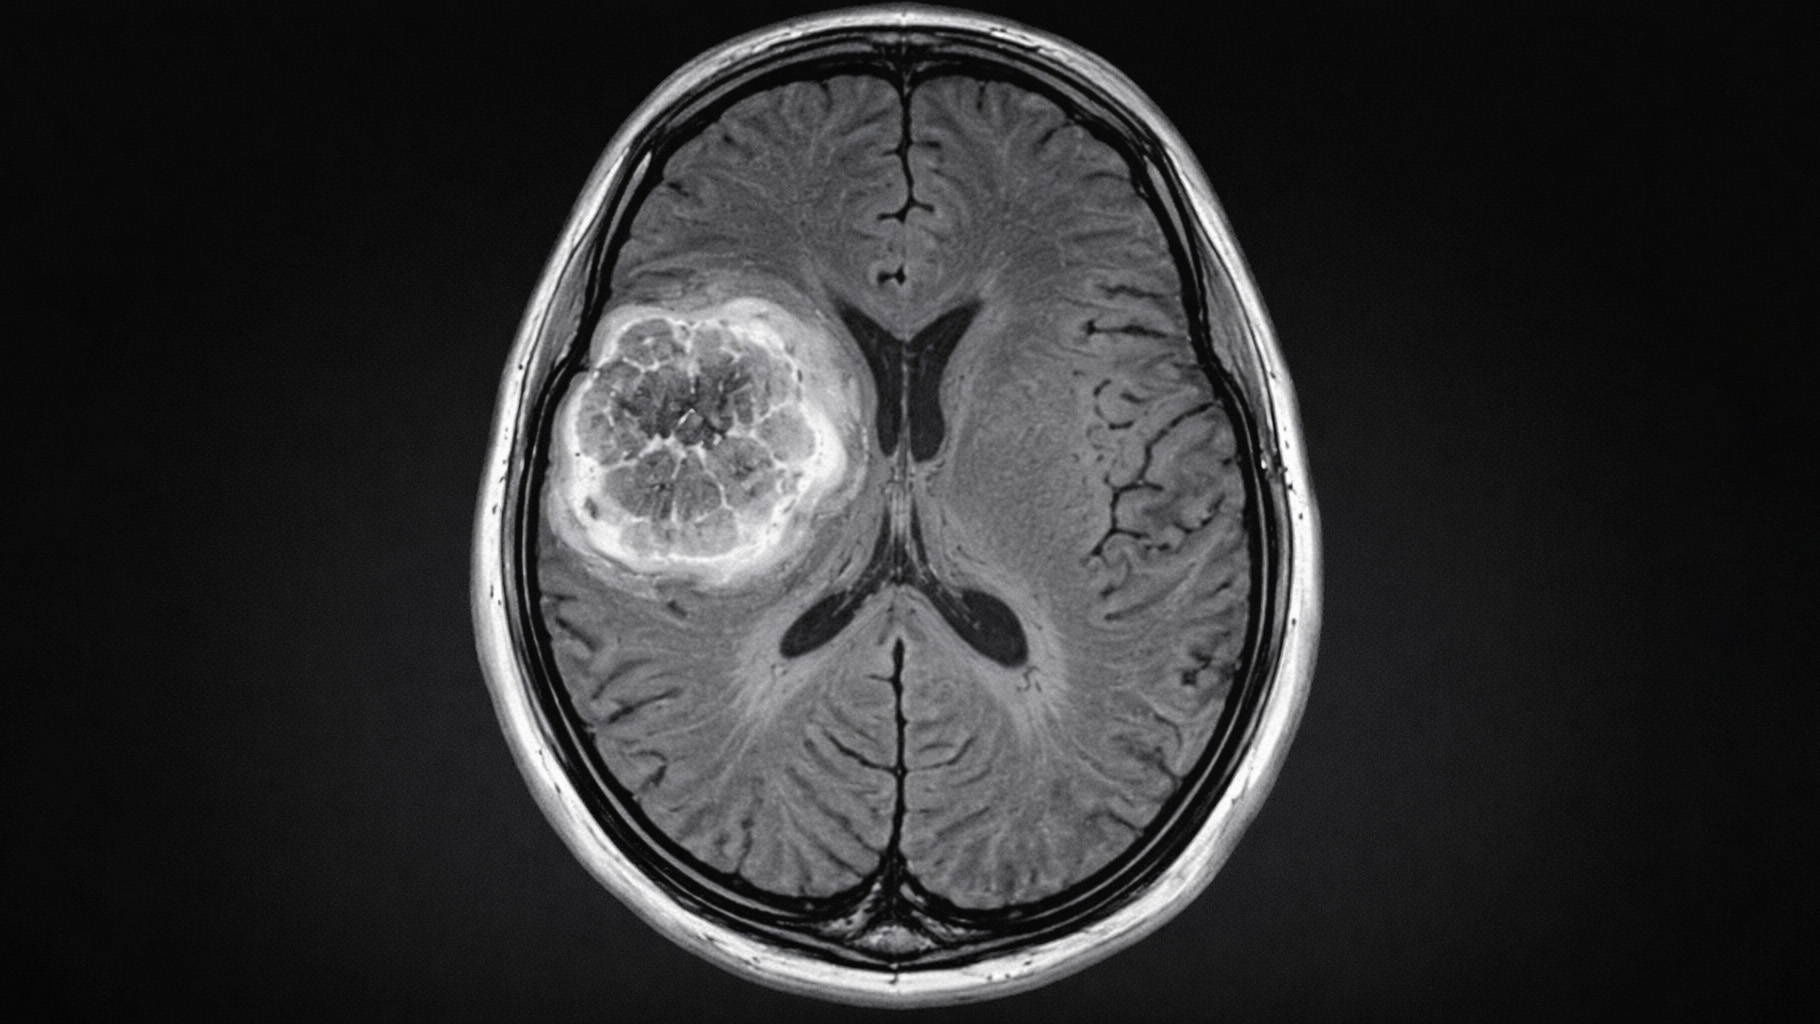

In contrast, the linear no-threshold (LNT) model, which traces back to Herman Muller’s work, assumes that even the smallest doses of radiation or carcinogens can cause harm, with no safe level of exposure. The LNT approach has dominated the shaping of public health policies, yet it is based on a flawed understanding of biology and ignores the body’s ability to repair damage from low-dose exposures.